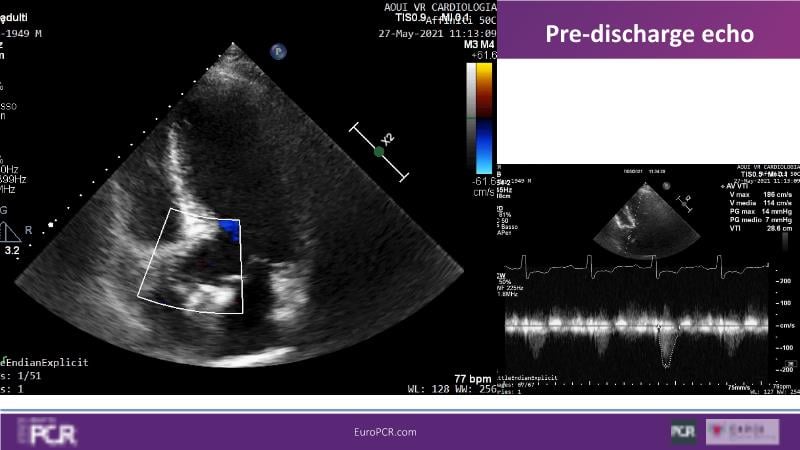

Discover the key factors to consider in selecting the optimal valve and implant technique for transcatheter aortic valve implantation (TAVI) to achieve optimal procedural outcomes. Gain insights into the impact of device choice and implantation technique on coronary access following TAVI and learn valuable strategies for tailoring your TAVI technique to complex scenarios, including bicuspid aortic valves, large and calcified anatomies, and ensuring coronary access.

- To learn how to tailor your TAVI technique to complex situations: bicuspid aortic valves, large, calcified anatomies and coronary access